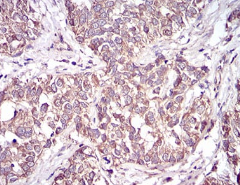

IHC    1/200 - 1/1000